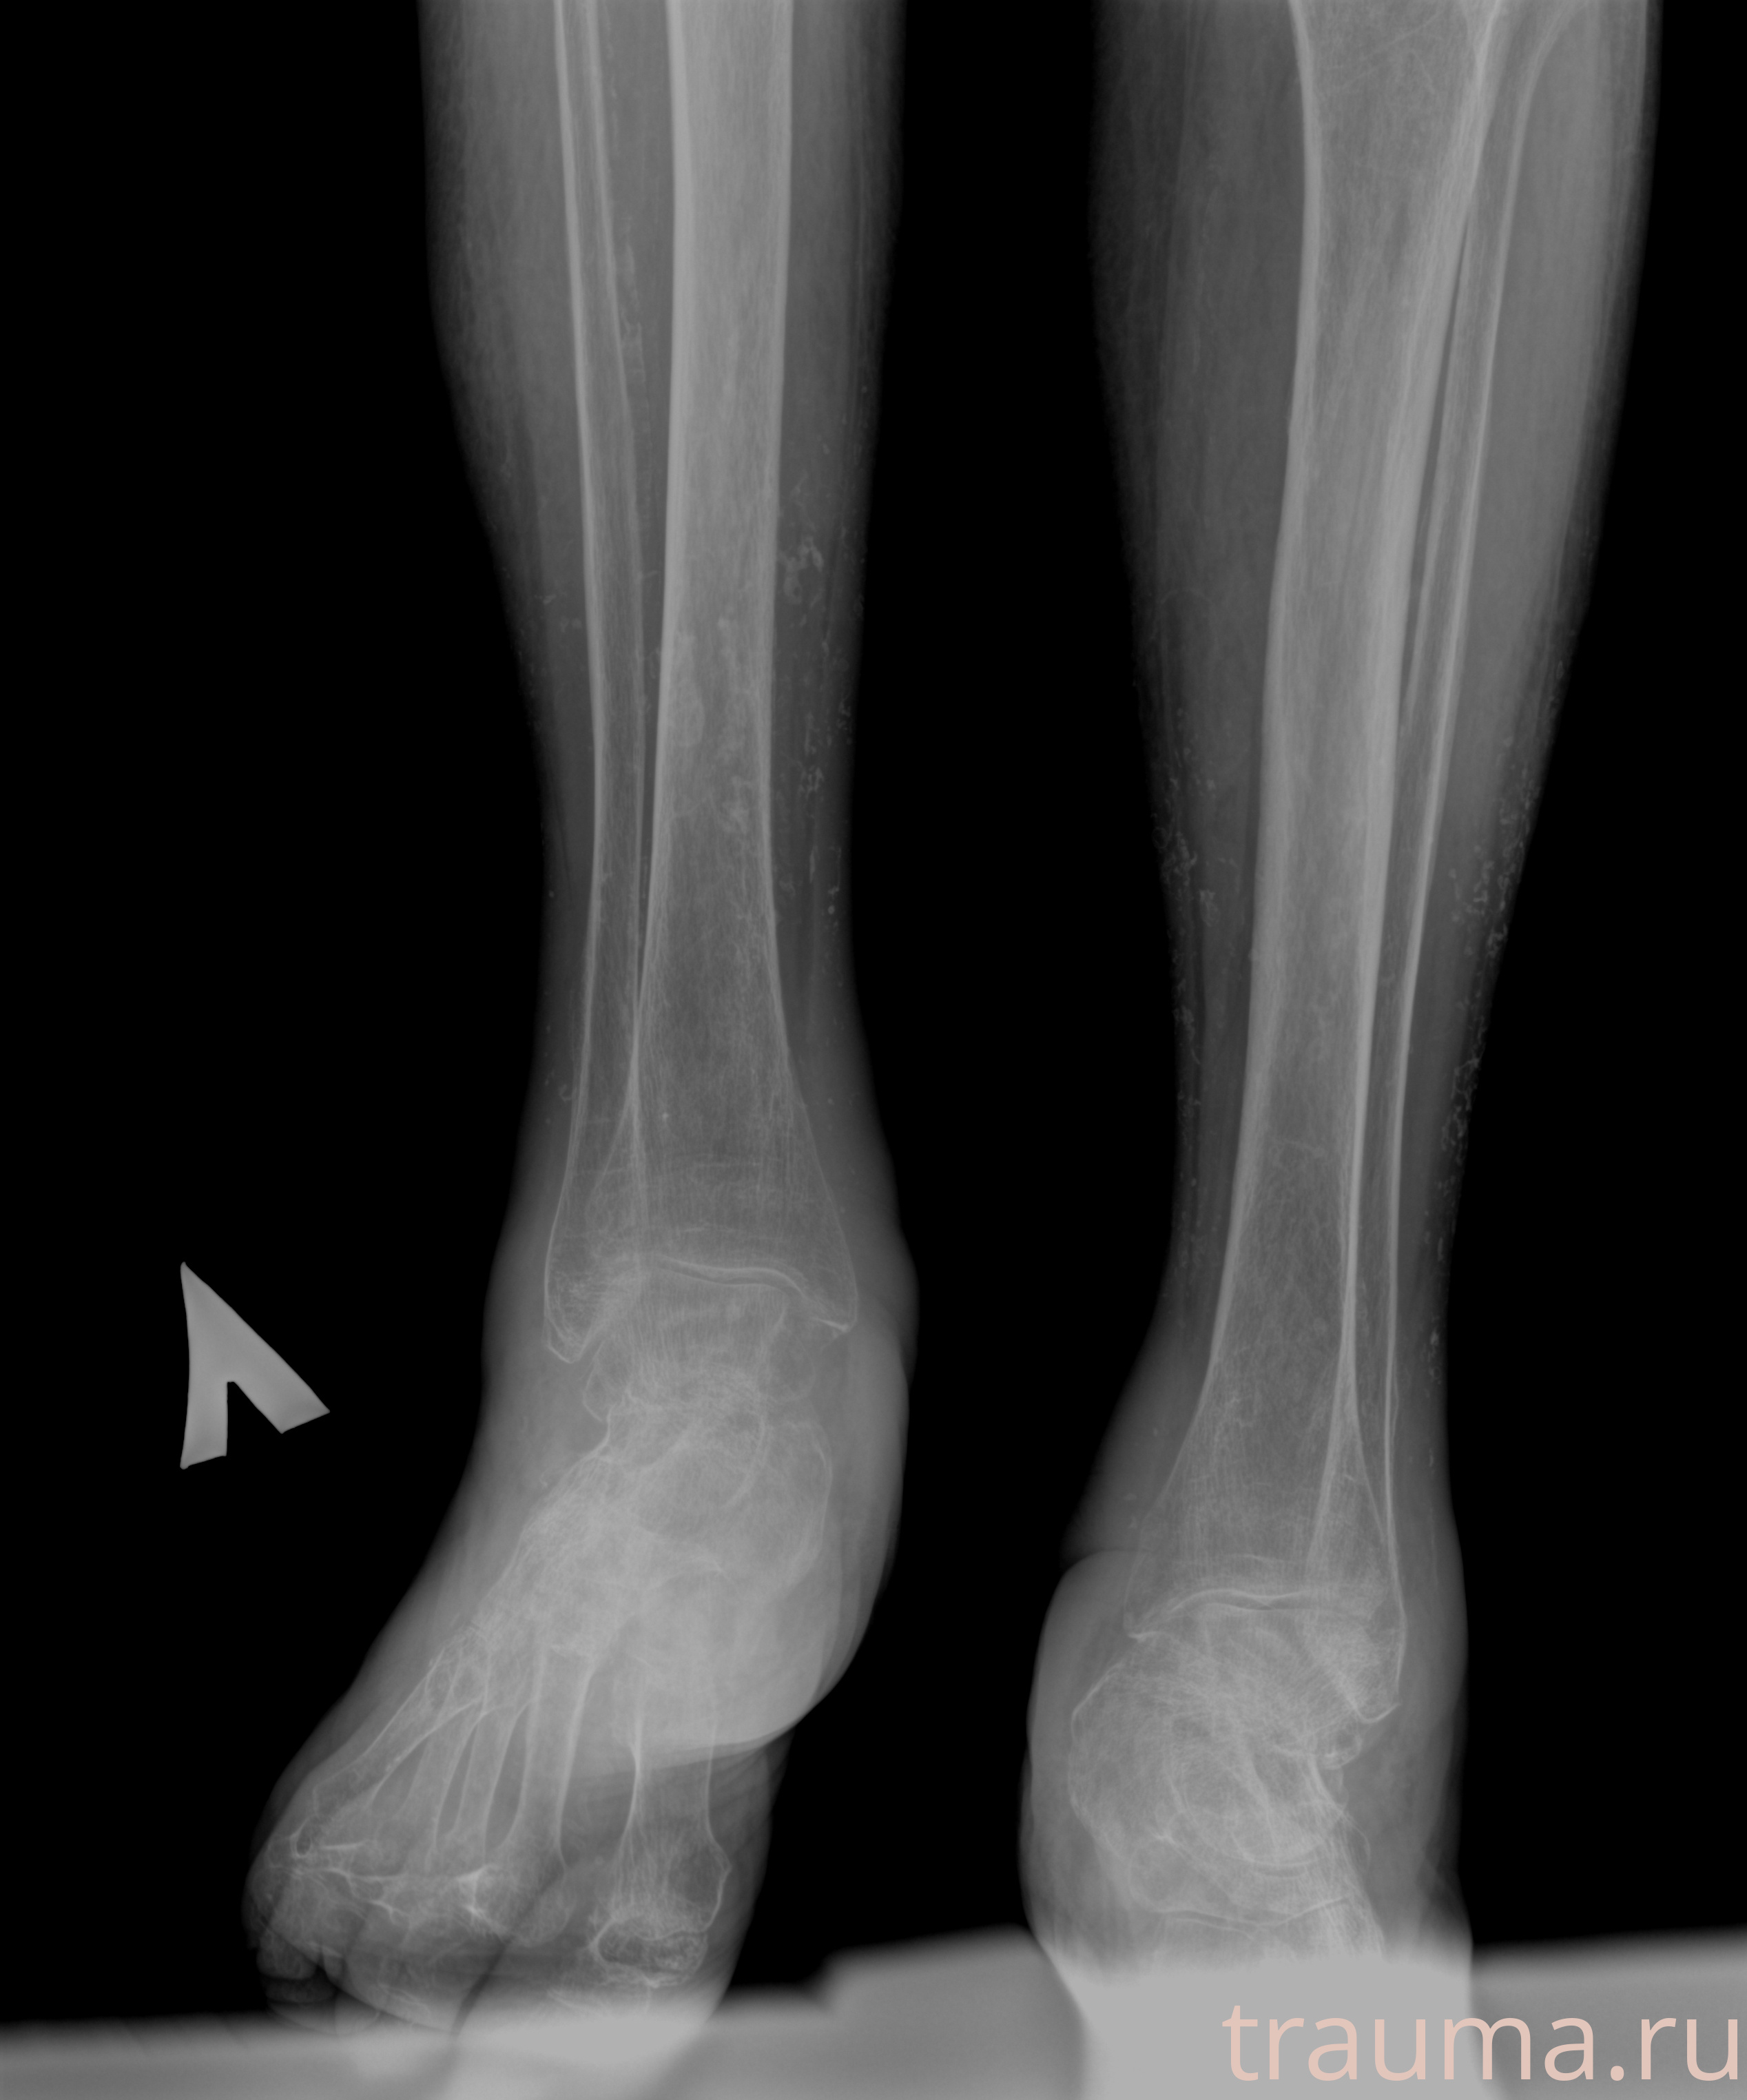

Рентгенограммы

Рентген на дому: по вашему адресу приезжает врач-рентгенолог, травматолог-ортопед с мобильным рентгеновским аппаратом, проводит диагностику травмы или заболевания, делает необходимые рентгенограммы, дает рекомендации по дальнейшему лечению. Получить качественные снимки в домашних условиях возможно благодаря уникальной методике, разработанной МосРентген Центром для института  Склифосовского